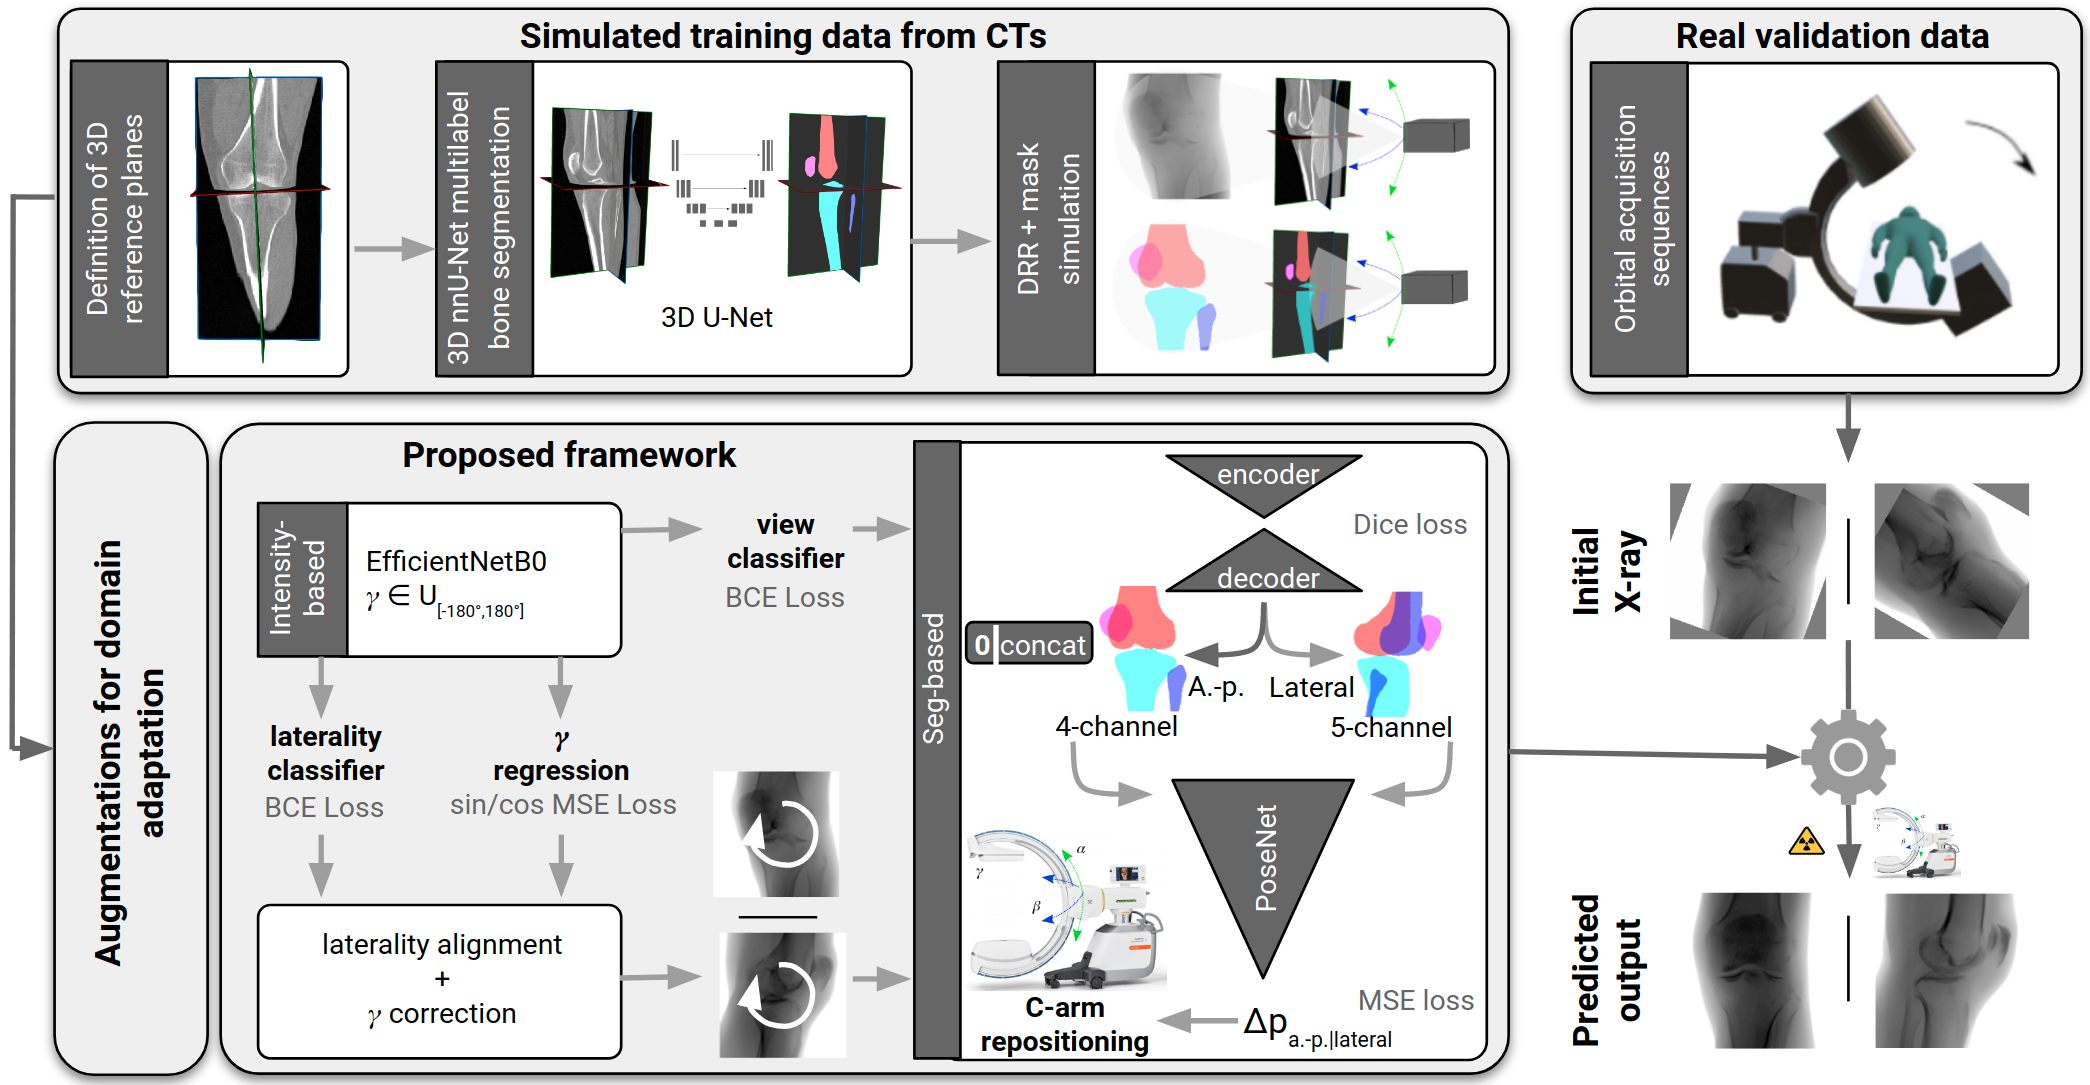

Surgical treatment of complicated knee fractures is guided by real-time imaging using a mobile C-arm. Immediate and continuous control is achieved via 2D anatomy-specific standard views that correspond to a specific C-arm pose relative to the patient positioning, which is currently determined manually, following a trial-and-error approach at the cost of time and radiation dose. The characteristics of the standard views of the knee suggests that the shape information of individual bones could guide an automatic positioning procedure, reducing time and the amount of unnecessary radiation during C-arm positioning. To fully automate the C-arm positioning task during knee surgeries, we propose a complete framework that enables (1) automatic laterality and standard view classification and (2) automatic shape-based pose regression toward the desired standard view based on a single initial X-ray. A suitable shape representation is proposed to incorporate semantic information into the pose regression pipeline. The pipeline is designed to handle two distinct standard views simultaneously. Experiments were conducted to assess the performance of the proposed system on 3528 synthetic and 1386 real X-rays for the a.-p. and lateral standard. The view/laterality classificator resulted in an accuracy of 100%/98% on the simulated and 99%/98% on the real X-rays. The pose regression performance was on the simulated data and on the real data outperforming intensity-based pose regression.

Recent developments towards robotic C-arms ask for automatic positioning methods. Many state of the art approaches require a patient-specific CT for intraoperative real-time simulation [4, 5, 8] or 2D-3D registration [2, 7, 16], external tracking equipment [6, 15], manual landmark annotation [1] or do not estimate an optimal pose but reproduce intraoperatively recorded C-arm views employing augmented reality [6, 19]. The inherent prior assumptions and severe inference with the clinical workflow hinder broad clinical applicability until today. In contrast to the majority of anatomical regions, the standard planes of the knee are not orthogonal to each other. The a.-p. standard view is characterized by symmetric projection of the joint gap, femoral and tibial condyles. The tibia surface projects line-shaped and the medial half of the fibula head is superimposed by the tibia. In the lateral standard view, both femoral condyles are aligned and the joint gap is maximized. Automatic deep learning-based positioning for standard views involves specific challenges for image understanding due to overlapping anatomical structures, the presence of surgical implants, and changing viewing directions and showed to benefit from extracting semantic information [10]. Inspired by that and considering that standard views of the knee anatomy are characterized by the shape information of the individual projected bones, we propose a complete framework to fully automate the C-arm positioning tasks during knee surgeries (Fig. 1). Our contribution is 4-fold: (1) We propose a novel framework that enables simultaneous automatic standard view classification, laterality classification, in-plane rotation correction, and subsequent view-independent shape-based C-arm positioning to the desired standard view while requiring only a single initial X-ray projection. One pose regression network can handle two distinct standard views of the knee anatomy. A suitable segmentation representation for the knee anatomy is proposed to recognize correct standard views, which explicitly incorporates semantic information to reflect on the actual clinical decision-making of surgeons. Since intraoperative X-rays with reference pose annotations do not exist, the proposed framework is solely trained on simulated data with automatically generated pose annotations. (2) We show that the proposed approach outperforms view-specific shape-based and intensity-based pose regression. (3) We show that the proposed shape representation and augmentation strategies aid generalization from simulated training data to real cadaver X-rays. (4) We investigate the importance of individual knee bones on the overall positioning performance for two distinct standard views.

An overview of the complete framework for fully automated C-arm positioning towards desired standard views during knee surgeries is given in Fig. 1. The anterior-posterior (a.-p.) and the lateral standard view showed to be sufficient for various diagnostic entities [3].

(1) Field-of-view cropping: Prevents superposition of the other laterality in the projection domain. (2) Laterality alignment: Prohibits ambiguities during pose estimation. (3) Definition of 3D reference planes: Two independent raters defined the 3D reference planes in the CT volumes utilizing a DRR preview integrated into the open-source Medical Imaging Toolkit [21] with interactive plane positioning. They serve as ground truth pose reference during simulation. (4) 3D automatic bone segmentation: To compute automatic 3D segmentations, a 3D nnU-Net [9] is trained on a subset of 10 manually annotated CTs for the task of multilabel bone segmentation, segmenting the femur, tibia, fibula, and patella. (5) Suitable segmentation representation: The two femur condyles are not distinguishable in the shape-based representation, however, this is relevant for optimal lateral view recognition. Annotating the condyles as line features would result in an increased manual labeling effort in the projection domain. Alternatively, we propose to incorporate this information in the segmentation by separating the femur annotation symmetrically along the femoral shaft (Fig. 2(a)). This results in one additional segmentation label for the lateral standard to recognize condyles’ congruence and derive the directional pose offset. (6) DRR and mask simulation: DRRs are simulated for varying angulations of orbital and angular rotation around the defined reference standard. The DeepDRR simulation framework was extended to allow the forward projection of corresponding masks (Fig 2(b)).

2.2 Shape-based positioning framework:

The proposed shape-based positioning framework was trained jointly for both standard views (Fig. 1). It consists of two modules: The first is responsible for a view classification, in-plane rotation and laterality alignment, directly estimated from the image intensities. Thereby, pose ambiguities and data variation are addressed, simplifying the task for the subsequent module to estimate the optimal C-arm positioning for the desired standard view, employing shape features.

(1) Intensity-based multi-task classification and regression module: For simultaneous in-plane rotation regression, view recognition, and laterality classification, an EfficientNet-B0 feature extractor [18, 14] was extended with two binary classification heads with one output neuron, followed by sigmoid activation, and one regression head, with the same architecture, but 2 outputs, omitting the activation. The in-plane rotation is mapped to sin/cos-space to ensure a continuous Loss function during optimization. All training examples were aligned with the same laterality during data simulation which would otherwise result in pose ambiguities. Thus, to train the laterality classifier, the training examples were randomly flipped horizontally with and the corresponding label was adapted accordingly. The weights were optimized using Binary Cross Entropy Loss for the classification heads, and Mean Squared Error for the regression head.

(2) Shape-based pose regression: Following surgical characteristics for recognizing correct standard views of the knee, a view-independent shape-based pose regression framework was developed. The architecture is based on a 2D U-Net [12] with two view-specific segmentation heads, because the segmentation labels differ for both views. The extracted shape features are used as input for the pose regression network that outputs the necessary C-arm pose update (, , , ) to acquire the desired standard view [11].

Real X-rays for validation were sampled from single Siemens Cios Spin® sequences generated during 3D acquisition of 6 knee cadavers. Preprocessing consisted of (1) definition of 3D standard reference planes, (2) laterality check, (3) sampling of X-rays around the defined reference standards in the interval , and generation of ground truth pose labels. Since the Spin sequences are orbital acquisition sequences, only the orbital rotation is equidistantly covered in the validation set, while the angular rotation is constant for all X-rays sampled from the same sequence. The number of sampled X-rays per standard and view may differ, if the reference standard is located close to the edge of the orbital sequence (range: 102-124).

A complete framework for automatic acquisition of standard views of the knee is proposed that can handle several standard views simultaneously. The complete pipeline is trained on simulated data with automatically generated annotations and evaluated on real intraoperative X-rays. To bridge the domain gap, different augmentation strategies are suggested that address intraoperative confounding factors, e.g., the OR table. View-independent training and multi-label shape features improve the generalization from simulated training to real X-rays and outperform direct intensity-based approaches. View-independent networks result in more training data which showed to improve the generalization from simulated training to real X-rays. The 2-step approach increases robustness and simultaneously automates necessary preprocessing tasks like laterality and standard view recognition, which can be performed with very high accuracy on simulated (, ) and real data (, ). The approach is fast and easy to translate into the operating room as it does not require any additional technical equipment. Assuming that the surgeon acquires the initial X-ray with a pose offset within the capture range of , it has the potential to reduce time and unnecessary radiation during manual C-arm positioning. Furthermore, the segmentation features can serve as a sanity check and indicate the reliability of the pose regression result. Further experiments with a larger training set covering more anatomical variation, e.g., patella baja and different flexion angles [13], can potentially address observed failure cases.